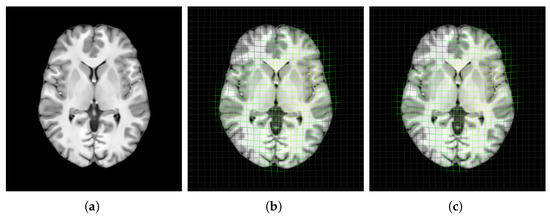

3.4.3. Usability of Saudi Brain Template

4.3. Usability of Saudi Brain Template